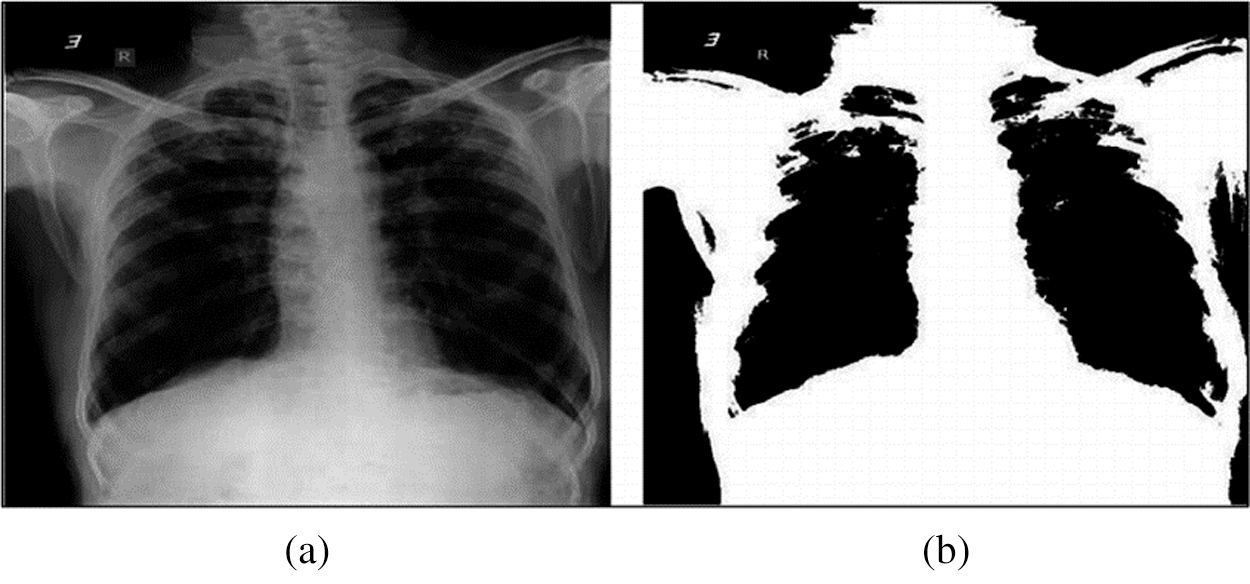

The overall HHO-based segmentation of chest X-ray images is presented in Fig. 8 and 9 presents an example of chest X-ray image before and after the HHO-based segmentation.

Figure 9: Example of chest X-ray image before and after HHO-based segmentation